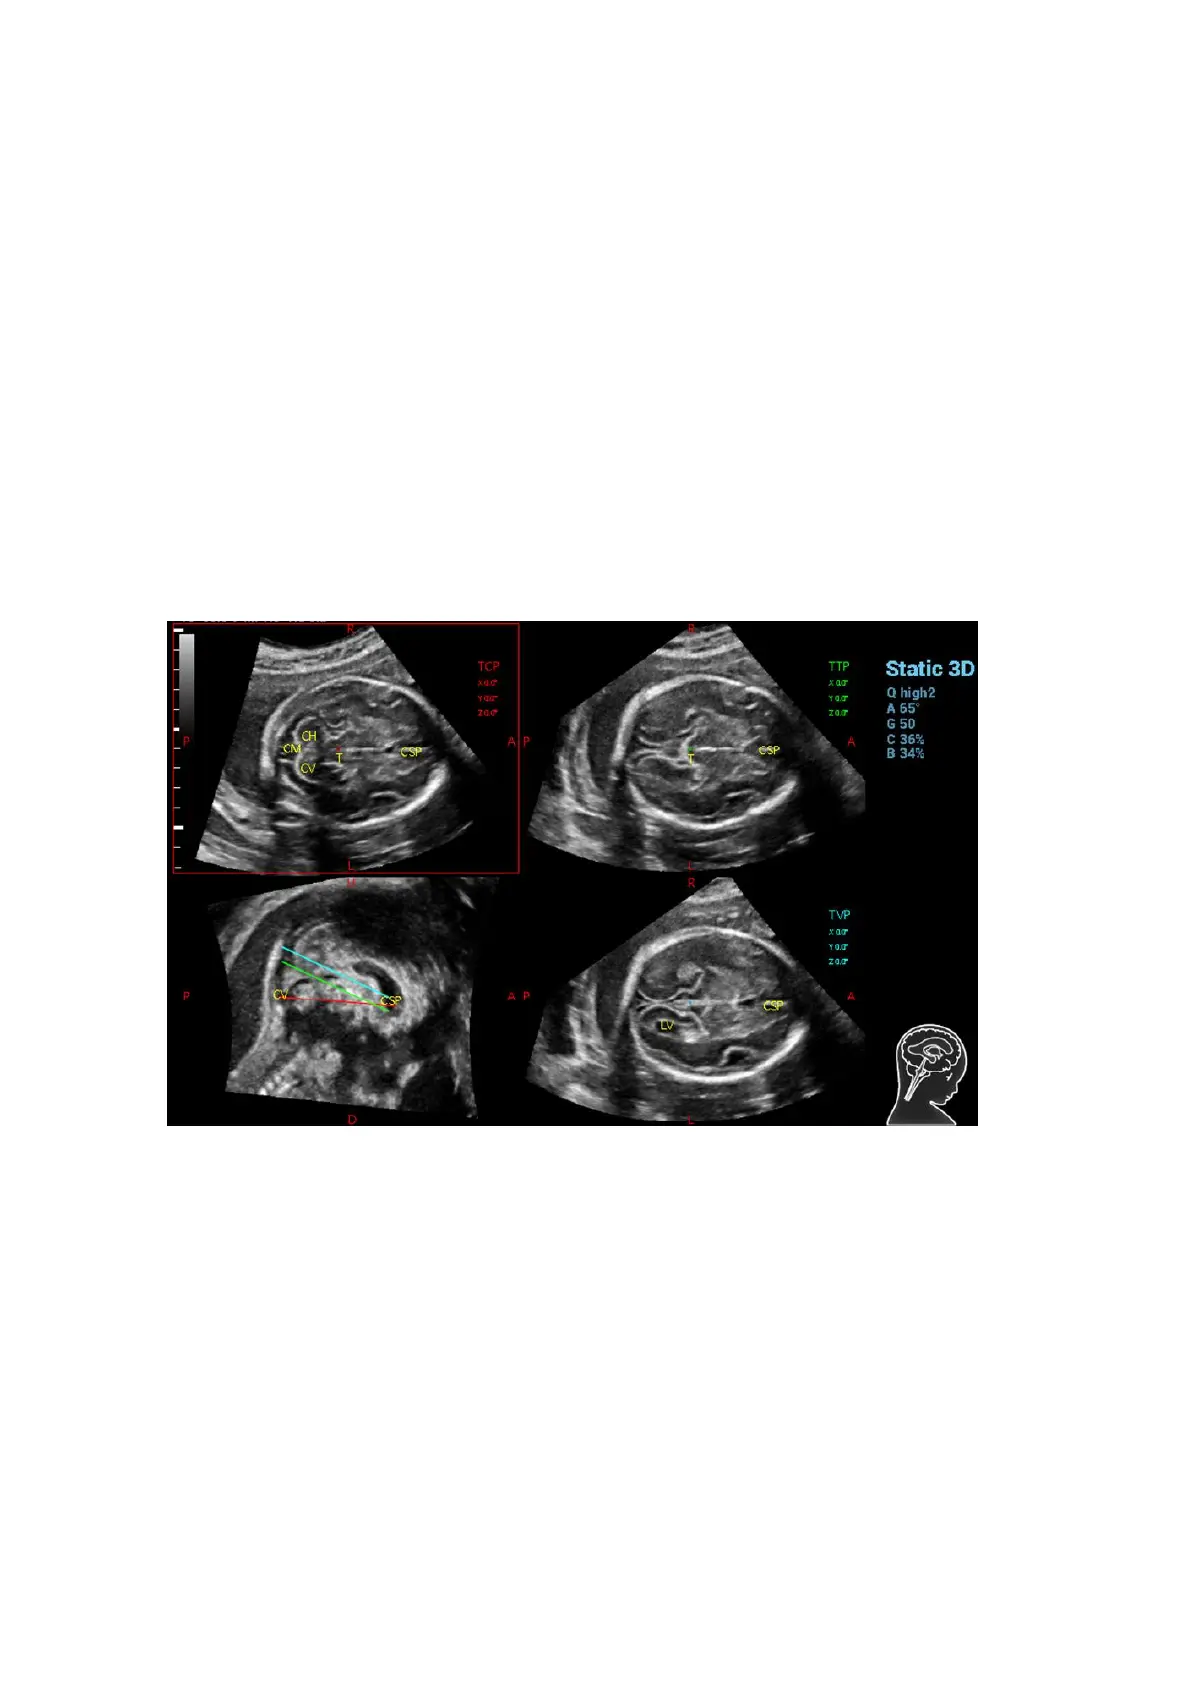

1. Acquire 3D data. Tap [S-Planes CNS] to enter the automatic detection of the mode.

2. Click [Auto Comment]. The comments appear on the image automatically.

Each of them is:

The orientation comments describe the location of the plane, referring to A (anterior), P

(posterior), L (Left), R (right), U (up), D (down).

Organ comments describe the position of the organ, referring to CSP (cavum septum

pellucidum), T (thalamus), CH (cerebellar hemisphere), CV (cerebellar vermis), CM (cisterna

magna), LV (lateral ventricles).